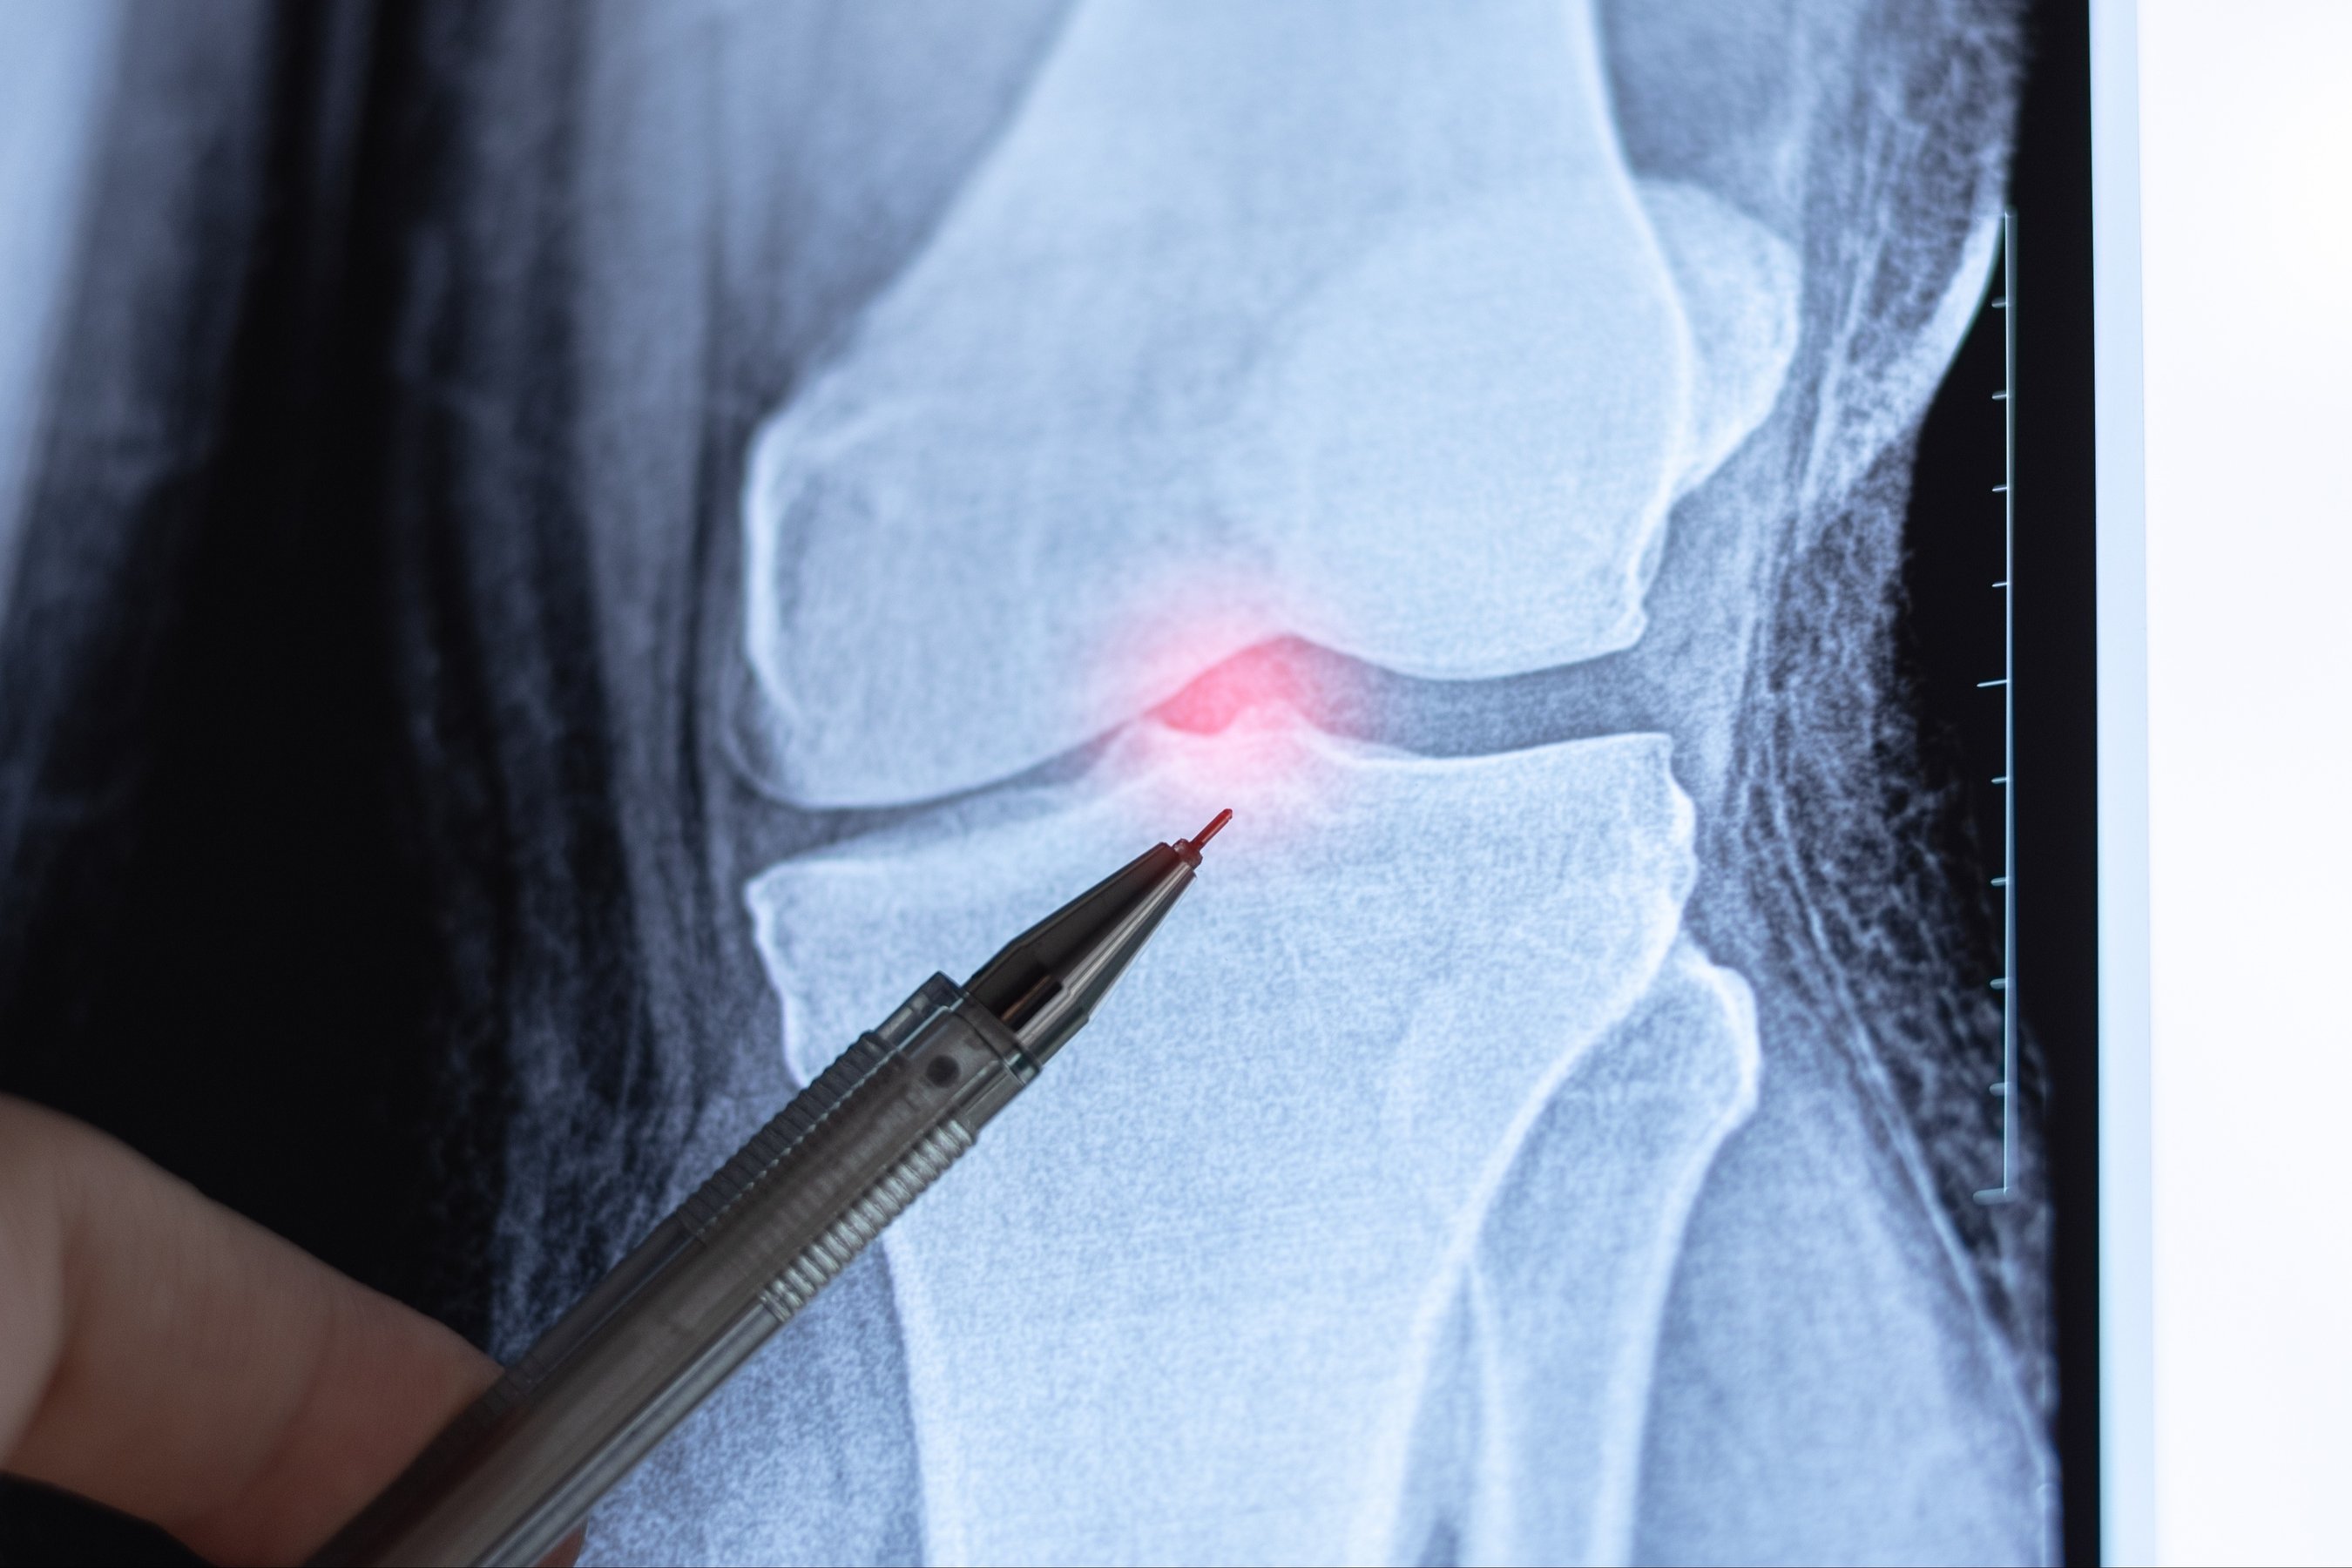

The patella, or kneecap, plays a critical role in knee movement by helping the quadriceps muscles extend the leg. It normally glides smoothly within a groove at the front of the thigh bone. When this tracking is disrupted, the kneecap can shift partially or completely out of place, resulting in patella instability.

Instability of the knee joint can make everyday movements feel unpredictable and unsafe. Without proper treatment, patellar instability can lead to cartilage damage, chronic pain, and recurring dislocations over time.

- Imaging studies: X-rays or MRI scans to evaluate bone structure, cartilage, and soft tissues